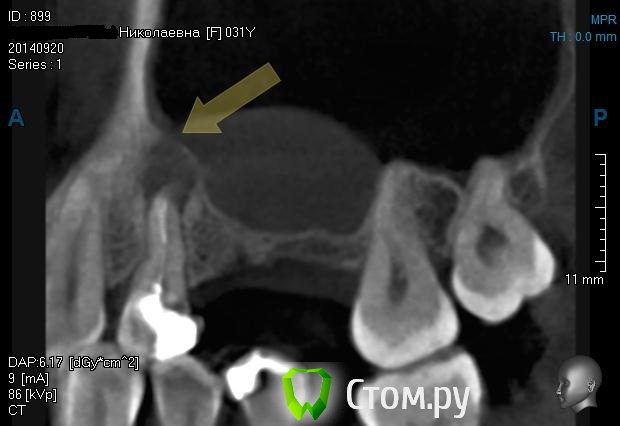

BORA Опубликовано 11 ноября, 2013 Поделиться Опубликовано 11 ноября, 2013 (изменено) Добавлю к теме случай:http://s57.radikal.ru/i156/1311/8f/f528f9ef3914.jpgпопробую vip-ctКак думаете,кисту не трогать- зашить?(jpg что то сохранил в паинте мелким,подскажите как увеличить?..спасибо) Изменено 11 ноября, 2013 пользователем BORA Ссылка на комментарий

kriokov Опубликовано 12 ноября, 2013 Поделиться Опубликовано 12 ноября, 2013 (изменено) Зачем тут подключать лора?на скрине не совсем четко видно, что в пазухе. Убрать зуб, кисту, закрыть сообщение. Через 1-2 мес кт сделать там и определиться с лором.И еще. Не факт , что перфорация будет. Иногда тонкий слой кортикального купола на кт не видно, но паца лучше заранее подготовить. Изменено 12 ноября, 2013 пользователем kriokov 4 Ссылка на комментарий

sergio Опубликовано 13 ноября, 2013 Поделиться Опубликовано 13 ноября, 2013 2 этапом после удаления,после устранения инфекции,повторное к/т.может гайморотомия в ЧЛХ.ЛОР здесь ни при чем,там одонтогенный гайморит,хотя данное к/т не особо информативно-про снята только бухта..только второй раз сделайте к/т 15 на 15, полностью придаточные пазухи.а то у вас там видно только бухту Ссылка на комментарий

Kostoprav Опубликовано 3 октября, 2014 Поделиться Опубликовано 3 октября, 2014 (изменено) убрал зуб, убрал оболочку( перфы слава Богу не обнаружил хотя по кт можно заподозрить) промыл бетадином и кинул на всякий пожарный полнослойный, ротированый лоскут с неба.так уже не первый раз- на кт полость кисты соединена с пазухой , а в реале тонкая, замыкающая, костная пластинка все же есть) Изменено 3 октября, 2014 пользователем Kostoprav Ссылка на комментарий

kriokov Опубликовано 3 октября, 2014 Поделиться Опубликовано 3 октября, 2014 кт полость кисты соединена с пазухой , а в реале тонкая, замыкающая, костная пластинка все же есть) пластинка тоньше , чем разрешающая способность кт, наверное поэтому и выглядит как сообщение с пазухой. Действительно часто такое. 1 Ссылка на комментарий